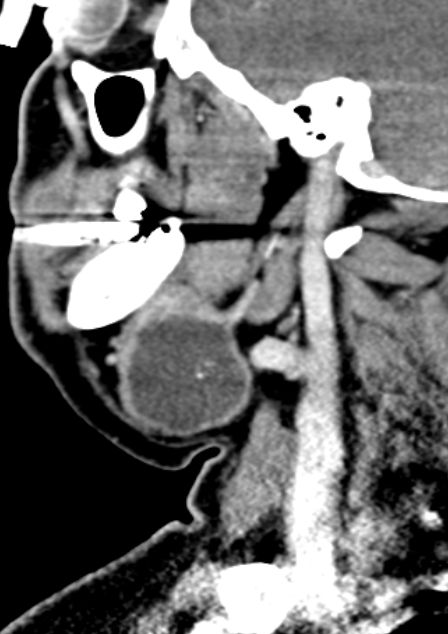

55-jähriger Mann mit einem Karzinom der linken G. submandibularis pT3 pNo Mo![]() |